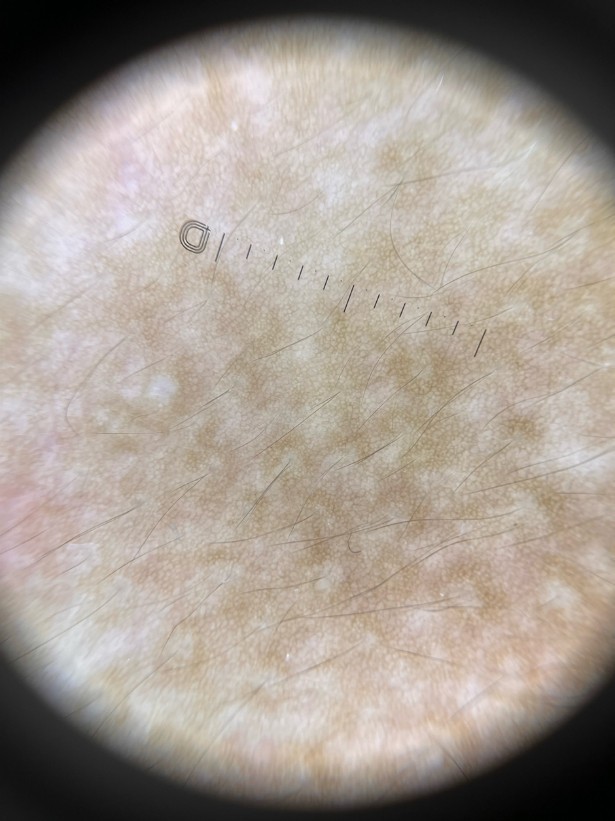

A 16-year-old boy presented with a hyperpigmented patch over his left chest since puberty. Examination showed a brownish patch to thin plaque with irregular borders and mild hypertrichosis over his left upper chest. There were also a few superimposed acneiform papules. Dermoscopy showed a well-defined pigment network with uniform thickness of lines and perifollicular hypopigmentation.